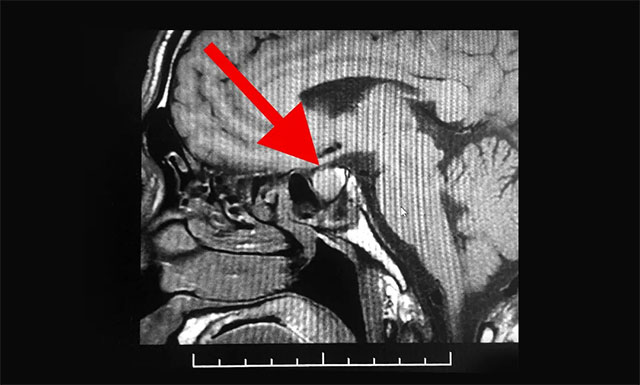

管先生因?yàn)榭人試?yán)重,于3月20日就診于浙江省某醫(yī)院,當(dāng)時(shí)掛的是呼吸科,經(jīng)過檢查,醫(yī)生說有些炎癥,吃些咳嗽藥就可以了。但與此同時(shí),醫(yī)生卻發(fā)現(xiàn)管先生的鼻子、手部和指關(guān)節(jié)都要比常人大很多,遂建議他去腦外科檢查,隨后他在該醫(yī)院又進(jìn)行了頭部MRI檢查,根據(jù)影像檢查結(jié)果,并結(jié)合其臨床癥狀,患者最終被確診為垂體瘤。

潘仁龍主任表示,患者容貌及四肢已發(fā)生很大改變,其四肢指關(guān)節(jié)粗大,聲音嘶啞,結(jié)合其影像檢查結(jié)果,手術(shù)指征明顯,應(yīng)盡早診療。